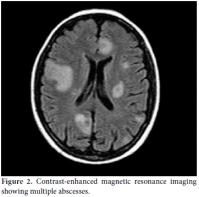

The polymerase chain reaction (PCR) tests for TB and cytomegalovirus (CMV) were negative, and the BAL specimen cultures were negative for bacterial, fungal, and mycobacterial infection. Cranial CT showed hyperdense mass lesions, and contrast-enhanced cranial magnetic resonance imaging (MRI) detected multiple hypodense nodular lesions that were abscess-like (Figure 2) and ring enhancing in the frontal mesencephalon region and cerebella regions. The results for toxoplasma immunoglobulin (Ig) M and IgG were also negative. Based on these findings, the patient's treatment was changed to linezolid and ceftriaxone. One month later, the patient's dyspnea had improved, and the lung infiltration was reduced. The patient was then discharged from the hospital with a prescription for oral TMP-SMX and cefixime treatment; however, a week later, she was readmitted with increased dyspnea and a 38.5 °C fever. On admission, we observed a seizure and left-sided hemiparesthesia; hence, linezolid, ceftriaxone, levetiracetam, and phenytoin were started. Cranial MRI showed a progression of the abscess lesions, especially in the right frontal region (2.5 cm diameter) and midline shift of the ventricle; therefore, urgent surgical decompression of the abscess was performed. A post-surgical examination of the blood cultures was performed at a private laboratory, and it showed Nocardia farcinica (N. farcinica) infection via a sequencing analysis of the 16S rRNA gene of isolates. The N. farcinica antibiogram was resistant to TMPSMX, ampicillin, and imipenem, so metilmicin was added to the patient's treatment. A good outcome was achieved following three months of intravenous treatment as the patient's brain abscess regressed. However, the left hemiparesis persisted.